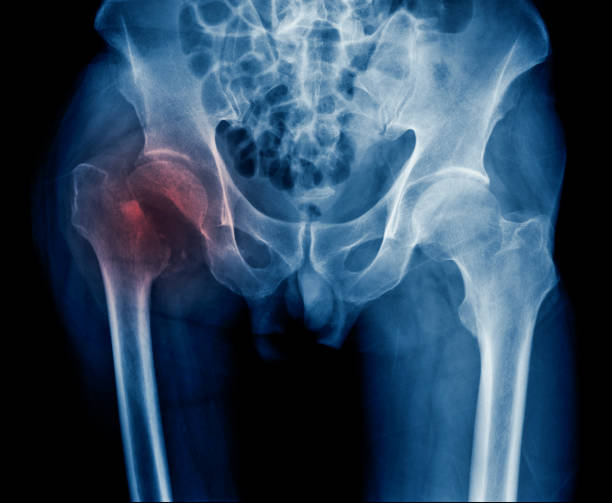

- Arthritis:One of the most common causes of pain in old broken bones is the development of arthritis, particularly post-traumatic arthritis. After a fracture heals, the affected joint may not function as smoothly as before, leading to wear and tear on the joint surfaces. This can result in arthritis, which can cause pain, swelling, stiffness, and reduced joint mobility. Changes in weather, including rainy and humid conditions, can exacerbate arthritis symptoms.

- Inflammation:Changes in weather conditions can influence inflammation levels in the body. Old broken bones may have residual inflammation, and fluctuations in weather can exacerbate this inflammation, leading to heightened pain. Individuals with osteoarthritis or rheumatoid arthritis may be more susceptible to weather-related inflammation.

- Healed misaligned fractures:If the broken bone is not properly aligned and healed in a malposition, it can cause chronic pain and joint dysfunction. This misalignment can lead to pain years later, particularly during certain activities or weather changes.